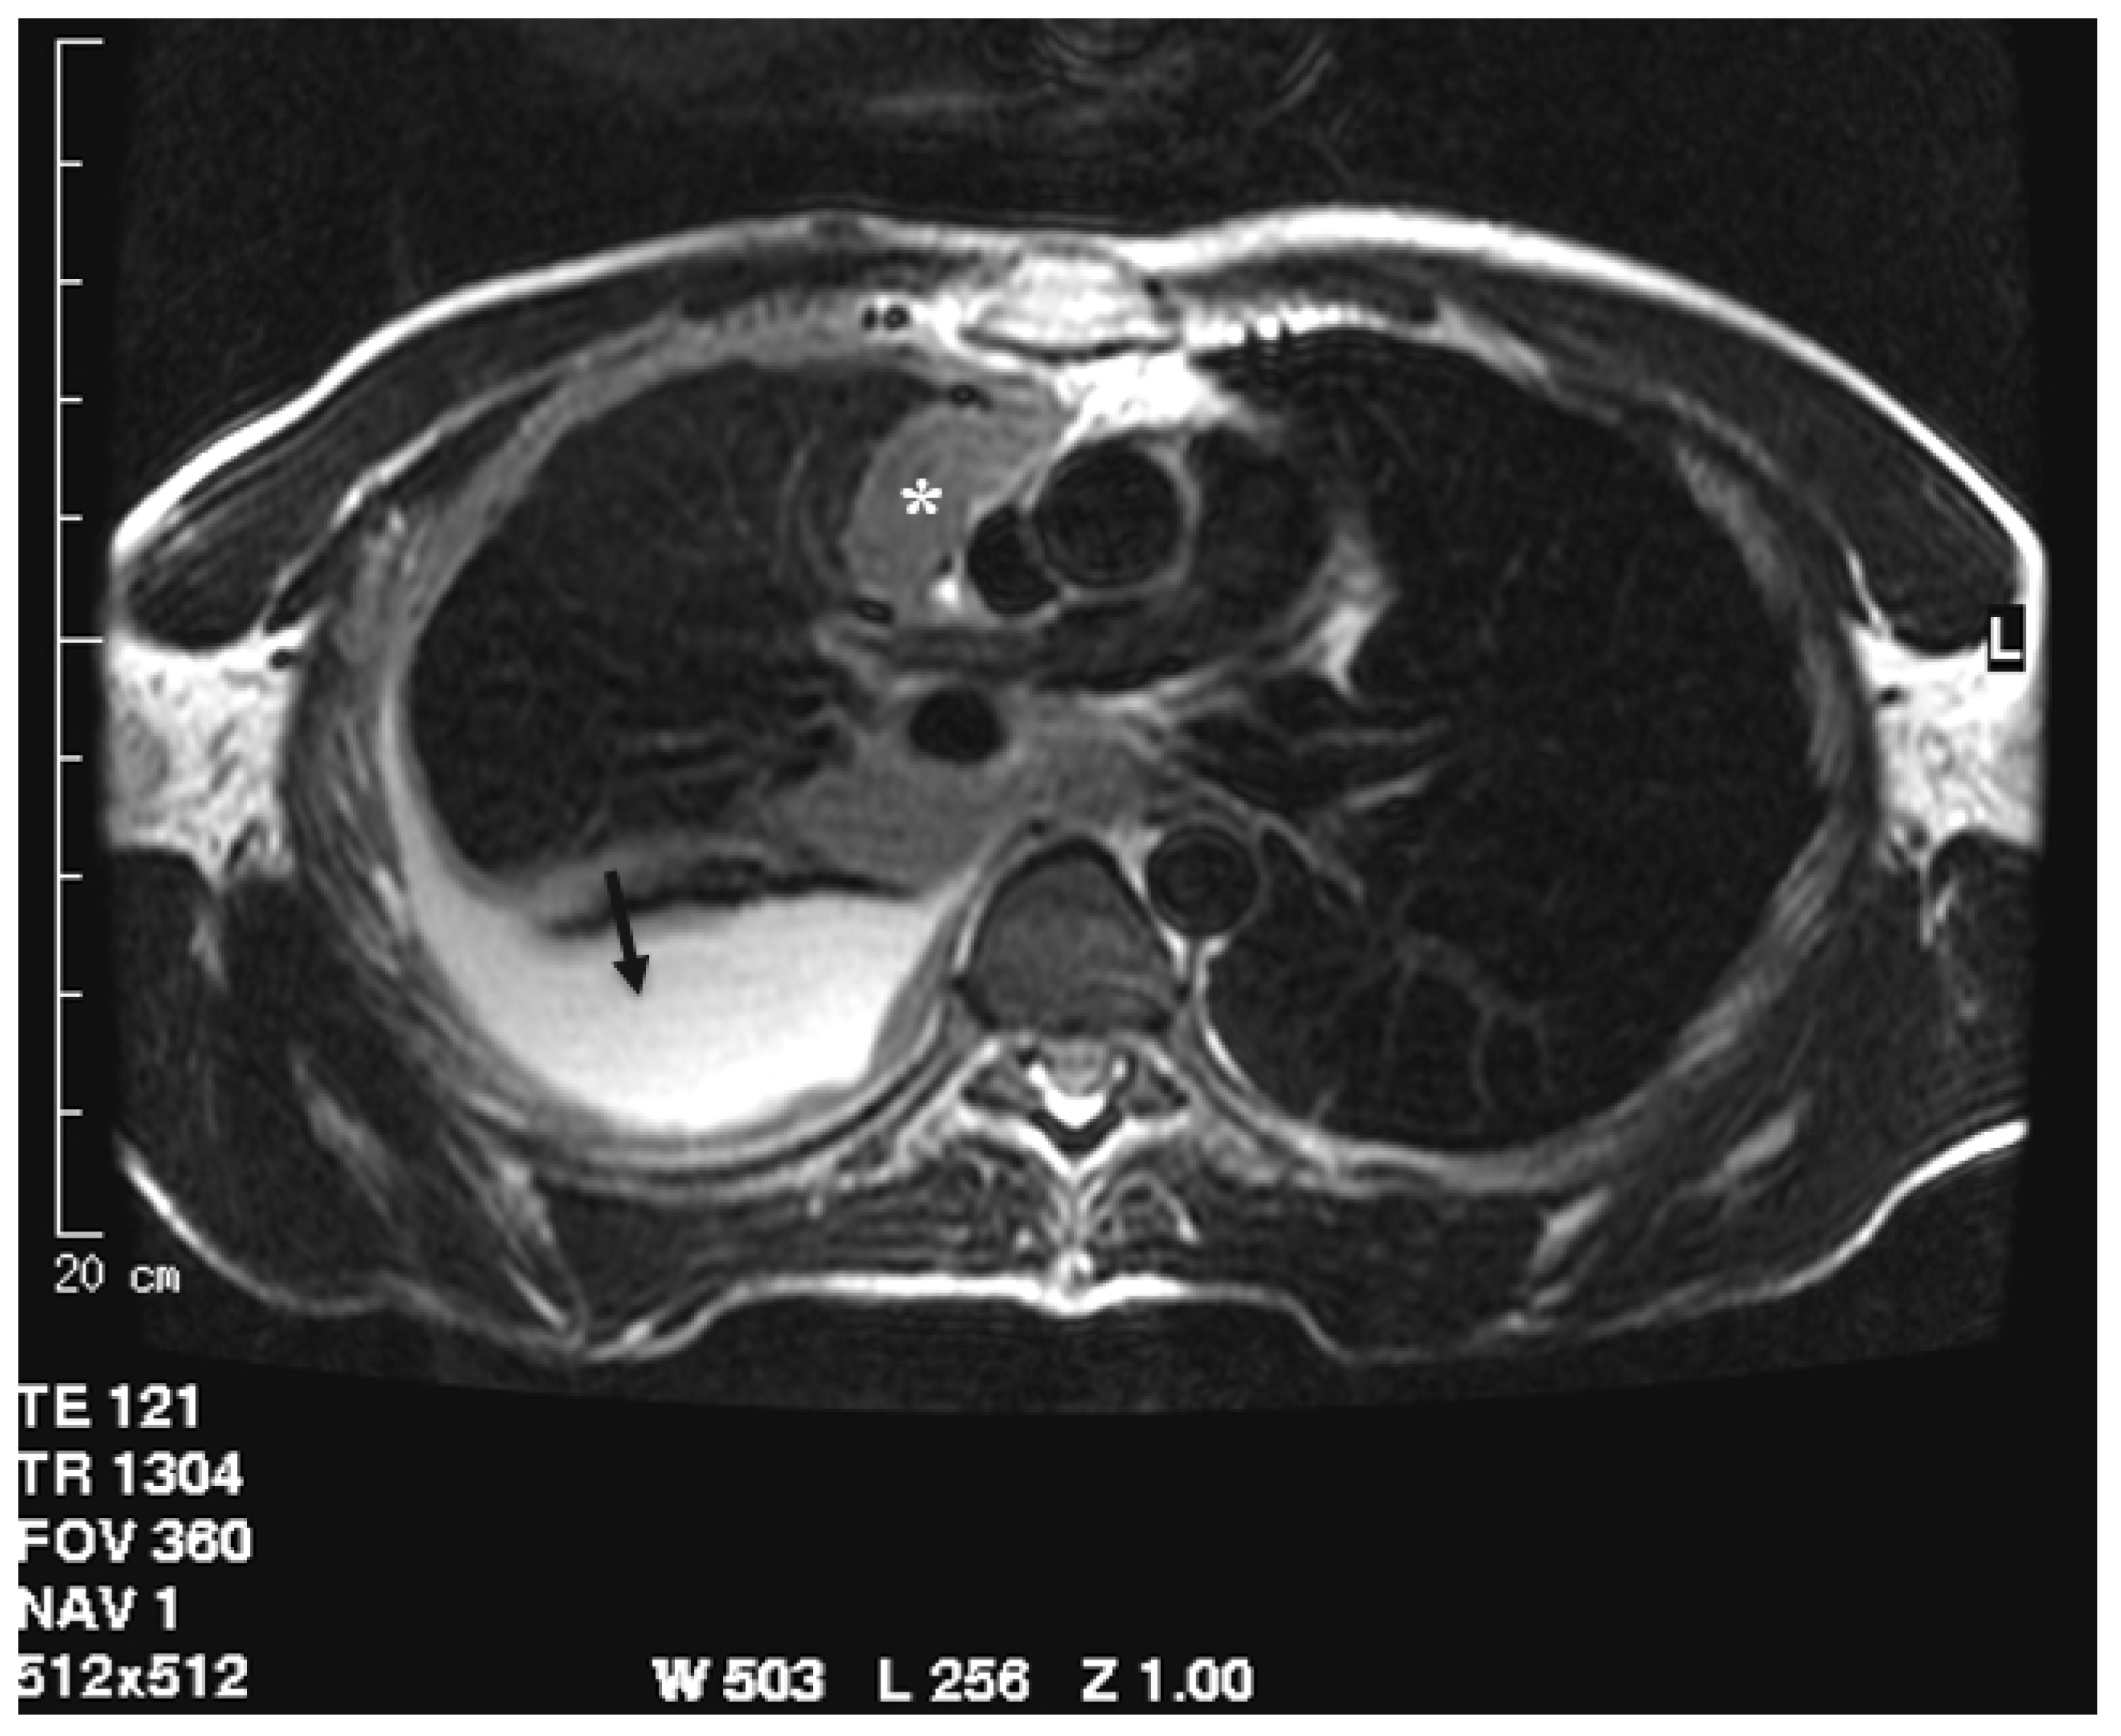

Figure 3.

T2-weighted image acquired in the axial plane clearly demonstrates circumferential pleural thickening with mediastinal pleura involvement (asterisk) and pleural effusion (arrow).